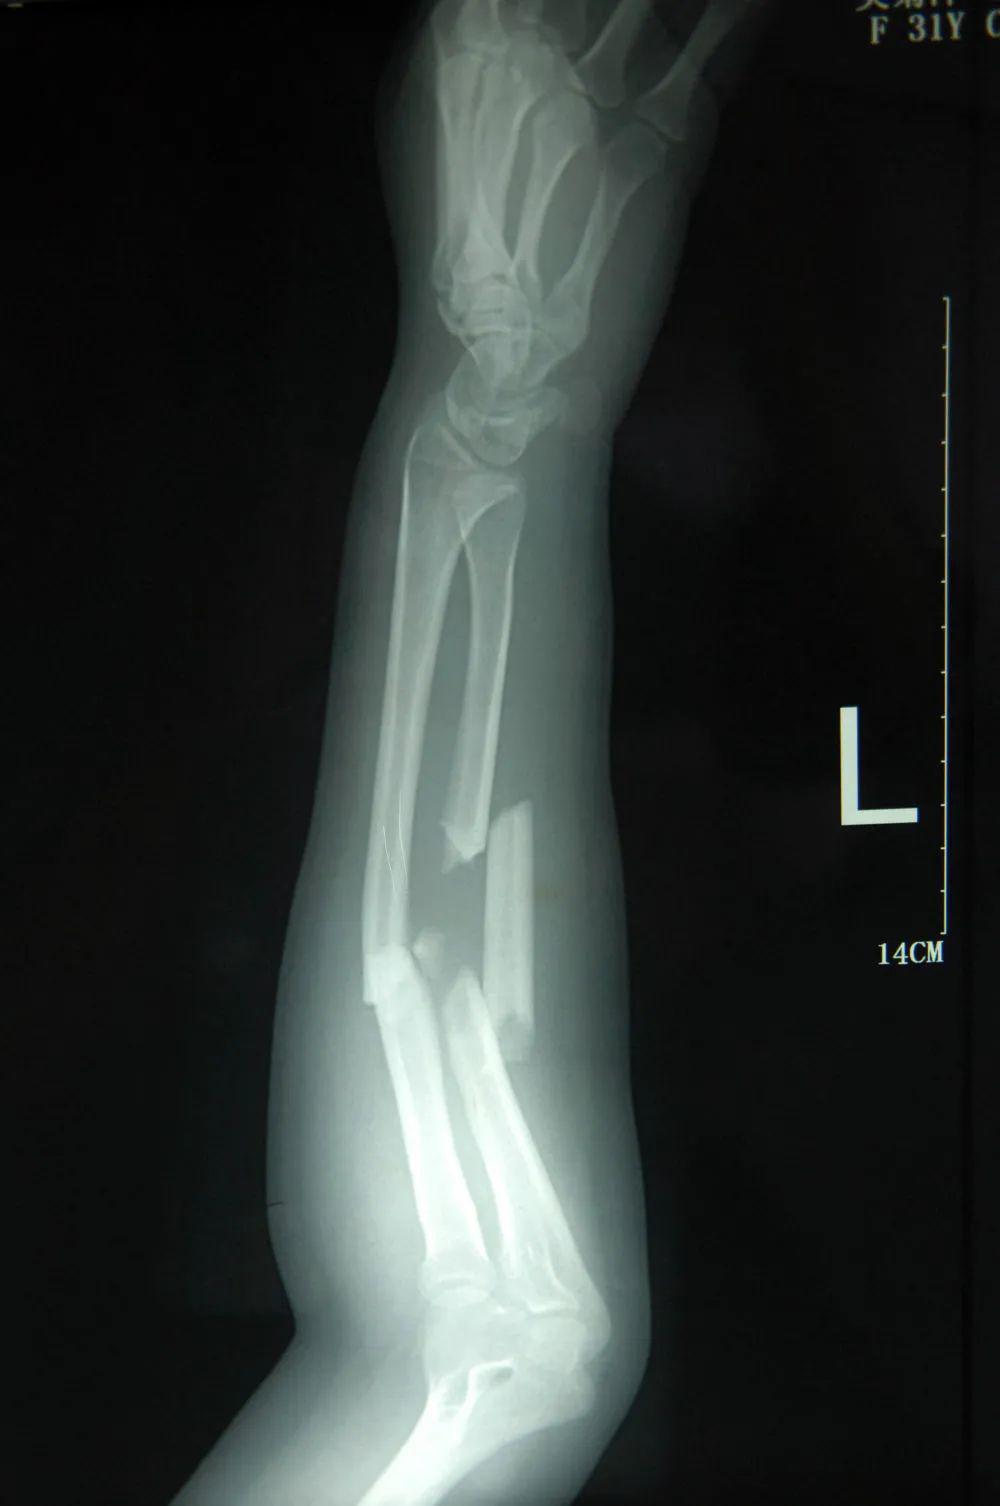

这奋力一接,让吴菊萍左手尺⻣桡⻣多段粉碎性⻣折,当场昏迷。

这是 2011 年 7 月 3 日拍摄的吴菊萍受伤左臂的 X 光片,医生诊断为手臂左尺桡骨多段粉碎性骨折。

当时,有热心网友做过计算:一个 2 岁的孩子重 30 斤,从 30 米高的 10 层楼掉落,当吴菊萍的手臂在接住她的那一秒,相当于接住了一个重达 300 多公斤的物体。